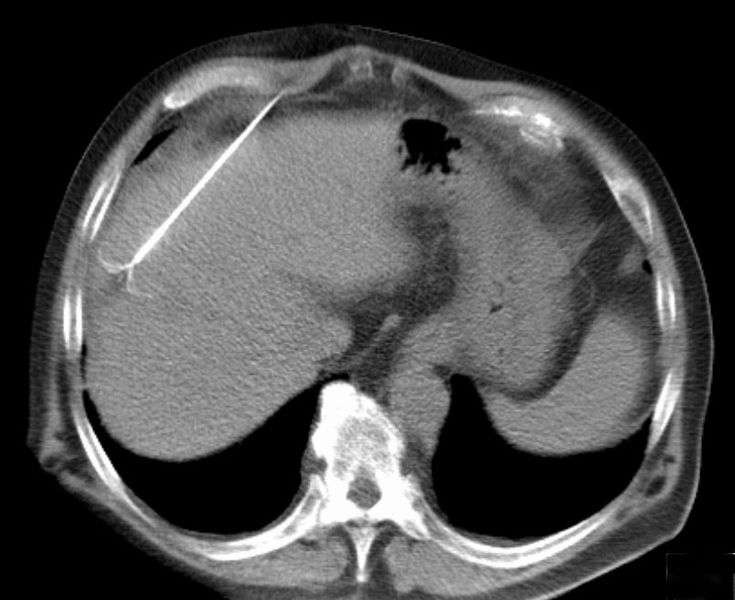

| CT scan showing radiofrequency ablation of a liver lesion |

Radiofrequency ablation (RFA) is a minimally invasive treatment, one of several types of ablation therapy, where surgery is not a good option. Guided by imaging, a thin needle or probe is inserted through the skin and into the tumor.The probe passes alternating electrical current (radiofrequency energy) through the tumor tissue generating heat at the site of the tumor. This causes tumor necrosis (cell death) and destruction of cancerous tissue.The dead cells eventually turn into a harmless scar.

RFA is used to treat numerous tumors including those in the liver, bone, kidney, and lung. A key advantage is it selectively destroys cancer cells while leaving healthy cells unaffected. The size and location of tumors are a factor in whether RFA can be used.